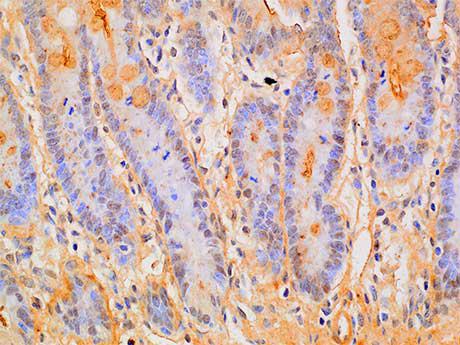

Smad1 belongs to the Smad family, which is a protein family of gene products similar to Drosophila genes, such as "Mother Against Peeling" (MAD) and the Caenorhabditis elegans gene SMA. One of the most important proteins regulating TGF - β ligand activity is the SMAD family of proteins. SMAD1 is one of the receptor activated Smads. It is also a signal transducer for BMP signaling and binds to several proteins involved in the ubiquitin proteasome system (UPS). It mediates the signaling of bone morphogenetic protein (BMP), which is involved in a range of biological activities including cell growth, apoptosis, morphogenesis, development, and immune response. In response to BMP ligands, Smad1 can be phosphorylated and activated by BMP receptor kinase. Its phosphorylated form forms a complex with Smad4, which is important for its function in transcriptional regulation.